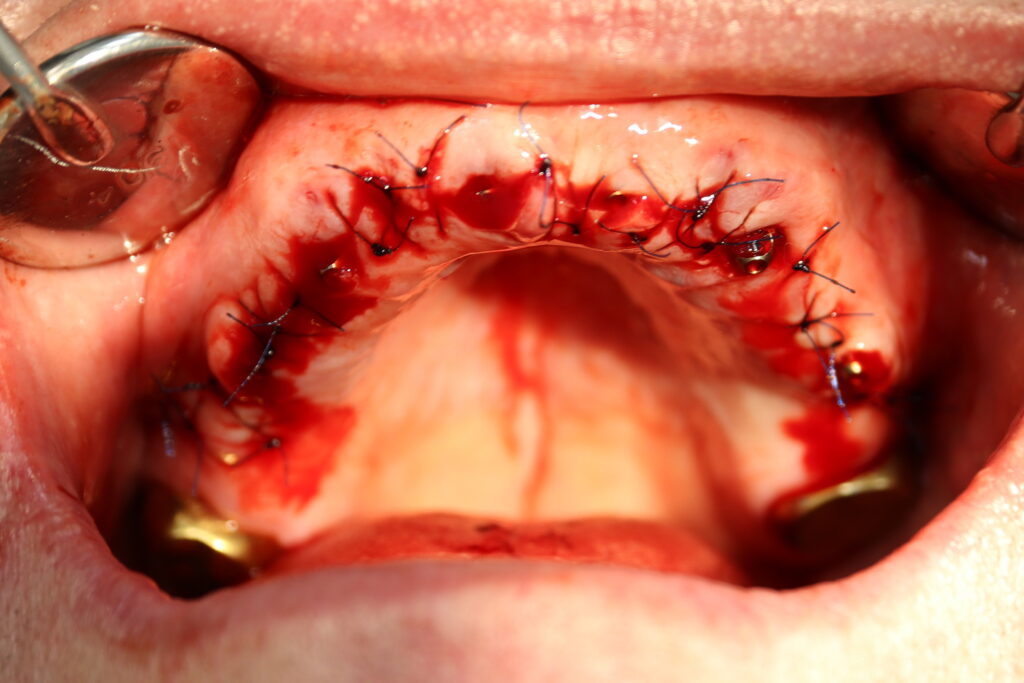

Это фото может содержать тяжелый для восприятия контент

процесс имплантации

Пациенту были установлены 6 имплантатов Megagen AnyOne по системе All-on-6 на верхней челюсти и 4 имплантата на нижней по классической двухэтапной методике.